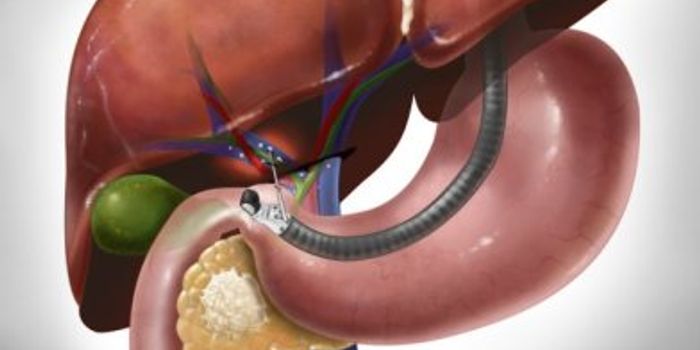

NOV 30, 2015Clinical & Molecular DXPancreatic cancer has one of the worst mortality rates of all cancer types, largely because the cancer spreads rapidly a ...

MAR 30, 2016Clinical & Molecular DXTo help treat pancreatic cancer, scientists are taking a step back to diagnose the disease before it becomes lethal. In ...

OCT 14, 2021Clinical & Molecular DXResearchers have unlocked a way of sniffing out cancer in patients with very-early-stage pancreatic cancer. This time, i ...

OCT 28, 2022CancerPancreatic ductal adenocarcinoma (PDAC), a highly aggressive type of pancreatic cancer, has a very poor prognosis due, a ...